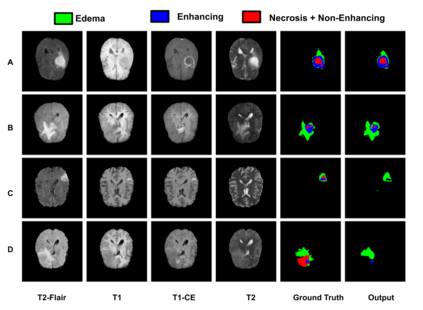

Gliomas are one of the most frequent brain tumors and are classified into high grade and low grade gliomas. The segmentation of various regions such as tumor core, enhancing tumor etc. plays an important role in determining severity and prognosis. Here, we have developed a multi-threshold model based on attention U-Net for identification of various regions of the tumor in magnetic resonance imaging (MRI). We propose a multi-path segmentation and built three separate models for the different regions of interest. The proposed model achieved mean Dice Coefficient of 0.59, 0.72, and 0.61 for enhancing tumor, whole tumor and tumor core respectively on the training dataset. The same model gave mean Dice Coefficient of 0.57, 0.73, and 0.61 on the validation dataset and 0.59, 0.72, and 0.57 on the test dataset.